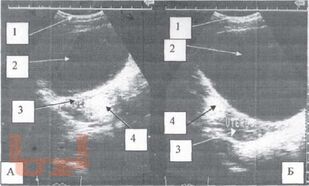

Томографическая диагностика опухолей и опухолевидных образований яичника у девочек

Диагностика и лечение опухолей и опухолевидных образований яичников у девочек и подростков является актуальной проблемой. Совершенство методов диагностики при данной патологии, хорошо зарекомендовавших себя во многих областях медицины, способствует внедрению их в клинику детской гинекологии, онкогематологии, детской хирургии.

Разнообразие средств диагностики, отличающихся по физическим данным и разрешающим способностям, а также по стоимости аппаратуры и самих исследований, часто ставит врача перед сложной проблемой определения необходимого минимума применяемых методов, последовательностью их выполнения и интегрирования результатов разных исследований в единую диагностическую концепцию.